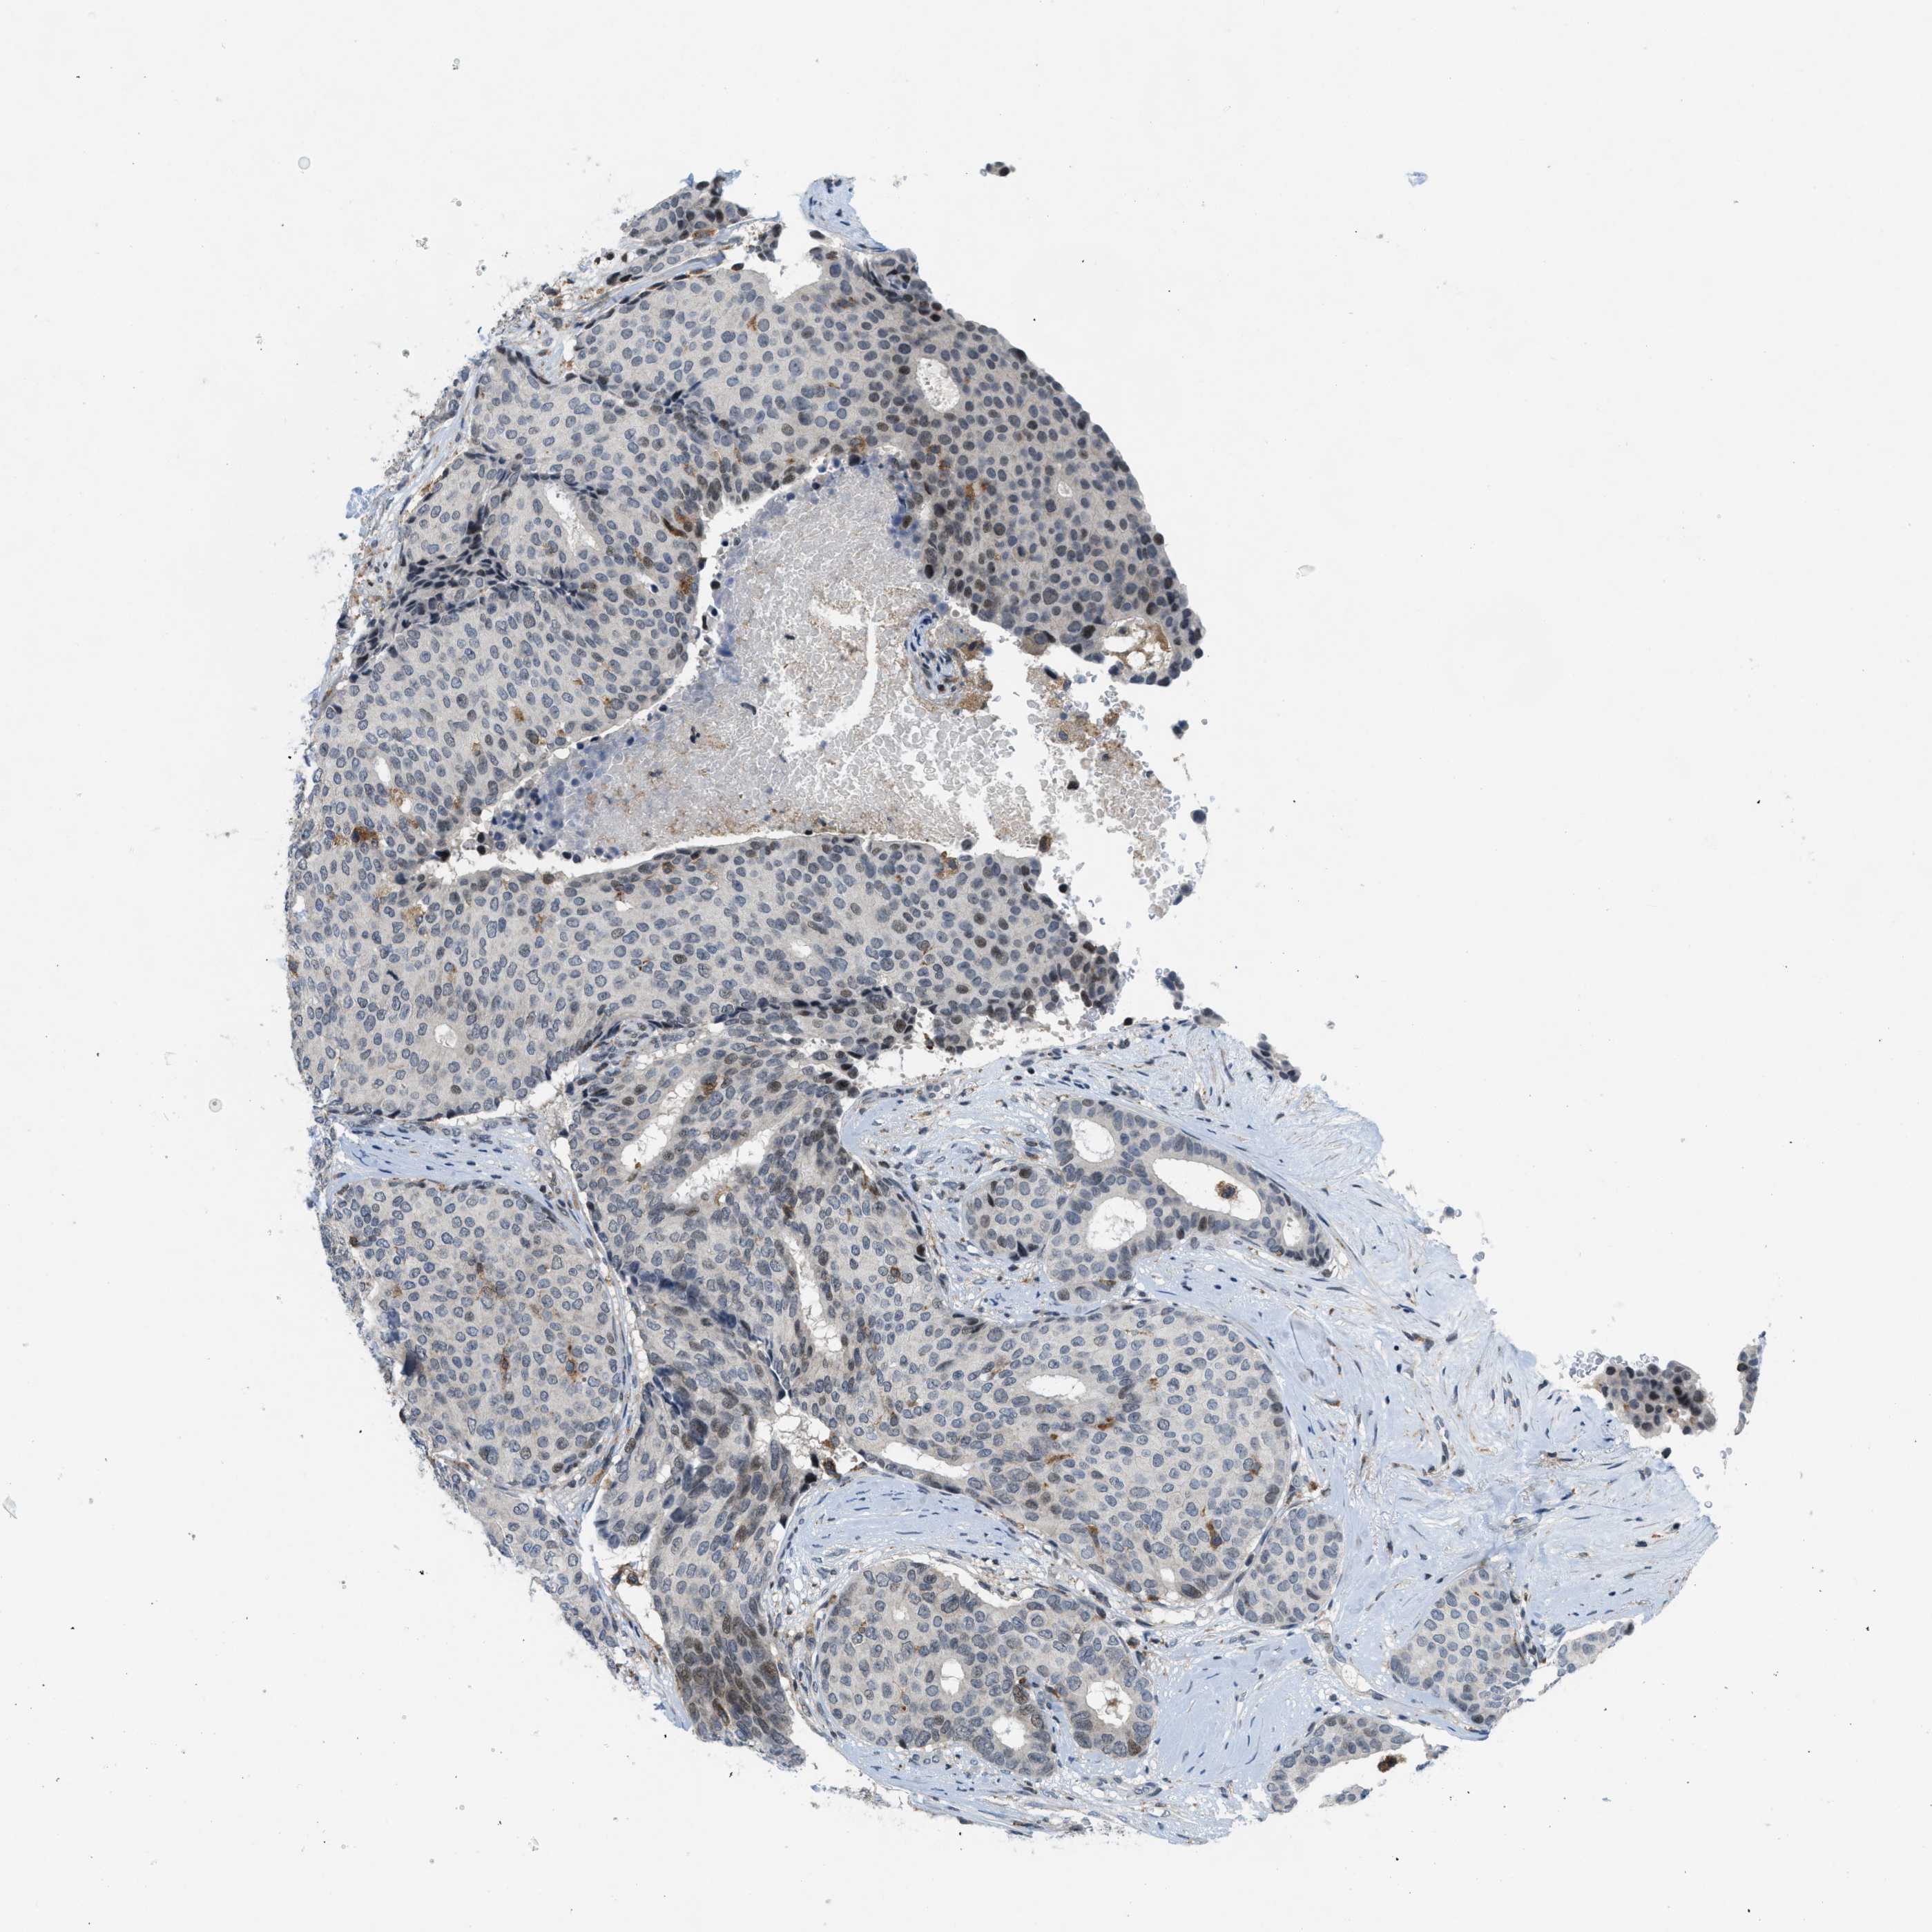

CANCER BREAST CANCER Show tissue menu

BRCA TCGA BRCA VALIDATION PROTEIN EXPRESSION

ANTIBODIES

AND

VALIDATION